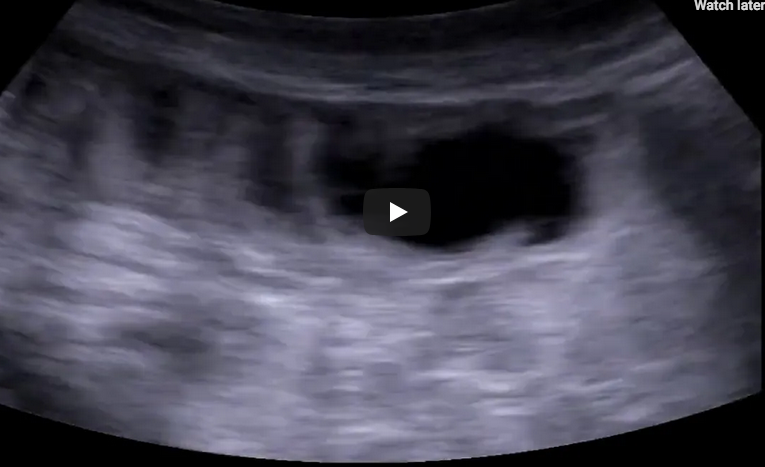

Student Image Challenge 60July 22, 2020Student Image Challenge 62August 4, 2020 Student Image Challenge 61 Student Image Challenge #61 1 / 1 Student Image Challenge #61 In B-mode ultrasound, fingerlike projections from the inner wall of the intestine also referred to as the “keyboard” sign are suggestive of… ? Diverticulitis Crohn's disease Bowel obstruction Ulcerative colitis Colonic abscess Incorrect ....Please see the correct answer highlighted Correct: Bowel obstruction B-mode ultrasound shows a fluid-filled bowel, with a diameter >2.5cm, ”to & fro” peristalsis and thick wall/plicae circulares. Your score isThe average score is 0% LinkedIn Facebook VKontakte 0% Restart quiz Case courtesy of Prof Adrian Saftoiu EFSUMBAdmin Related postsStudent Image Challenge 109Read more Comments are closed.